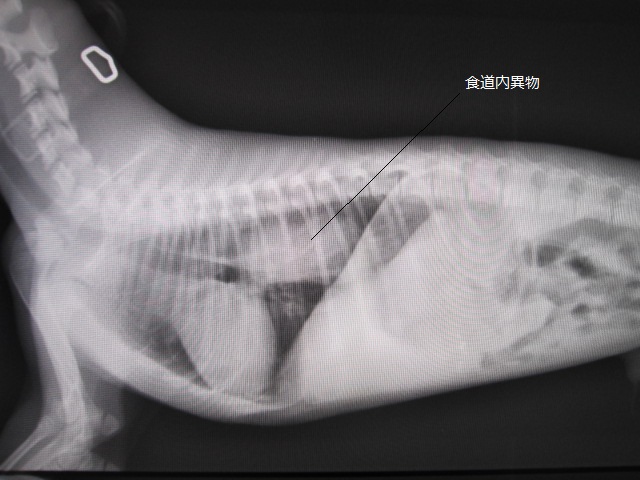

術前

術前のレントゲンです。

食道に異物があります。